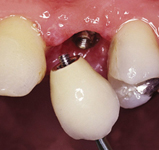

Náhrada jednoho zubu

Klasickým příkladem a indikací pro použití implantátu je ztráta jednoho zubu (v tomto případě v předním – frontálním úseku) v jinak zdravém, nepoškozeném chrupu.

Nejčastější příčinou takové ztráty je sportovní nebo dopravní úraz.

Náhrada jednoho zubu pomocí implantátu je možná také v postranním úseku chrupu. Při ztrátě většího počtu zubů ve frontálním nebo postranním úseku může být mezer uzavřena větším počtem jednotlivých implantátů.

Při ošetření pomocí jednotlivých implantátů zůstávají sousední zuby neporušené – intaktní. Při klasickém ošetření pomocí můstků musejí být tyto zuby obroušeny!